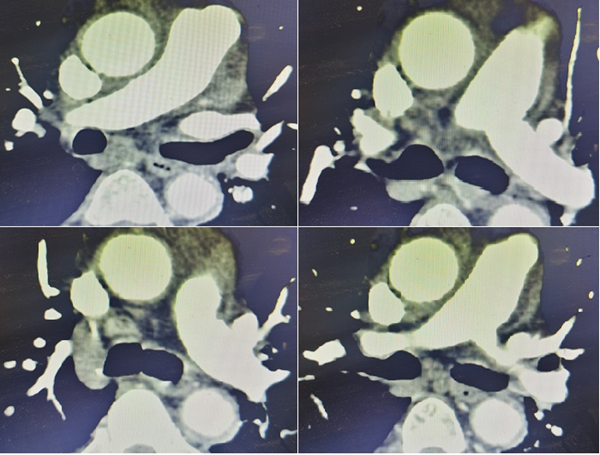

圖三:下腔靜脈濾器植入,肺動脈切開取栓

麻醉科迅速深靜脈置管,各類搶救藥品保障基本循環(huán)功能支持。血管外科行下肢靜脈造影示:左側腘靜脈股靜脈大量血栓形成,立即順利完成“下腔靜脈濾器植入術“。隨后,迅速麻醉誘導氣管插管消毒鋪巾,心臟外科立刻開胸,胸骨劈開后,患者出現(xiàn)心臟驟停。麻醉科手術室及心臟外科一邊胸內心臟按壓,一邊緊急建立體外循環(huán)。5分鐘后,體外循環(huán)順利工作,患者循環(huán)呼吸功能獲得支持。手術完整徹底取出左右肺動脈血栓,最長血栓長近20厘米,最粗直徑約1.5厘米。手術順利,術后4小時清醒,停呼吸機,拔除氣管插管。術后第二日轉入普通病房,術后第三天下床進行功能鍛煉。術后第七天,復查心臟超聲、肺動脈CTA 、生化常規(guī)等檢查提示手術結果滿意,各臟器功能正常,術后第十天患者順利康復出院。

圖五:術后肺動脈CTA示:左右肺動脈及各分支通暢,無血栓